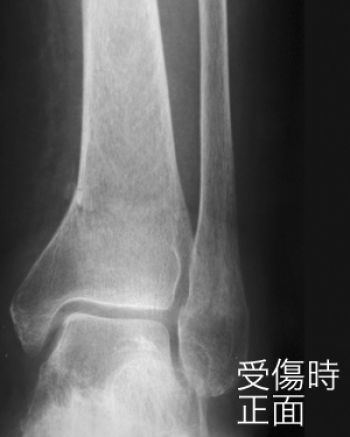

下腿骨遠位端部骨折

足関節部の骨折は、とくにスポーツ外傷で多発します。

解剖学的状態への回復に失敗すると、足関節の動揺性や、変形性関節症を残し、機能障害を生ずることもある。